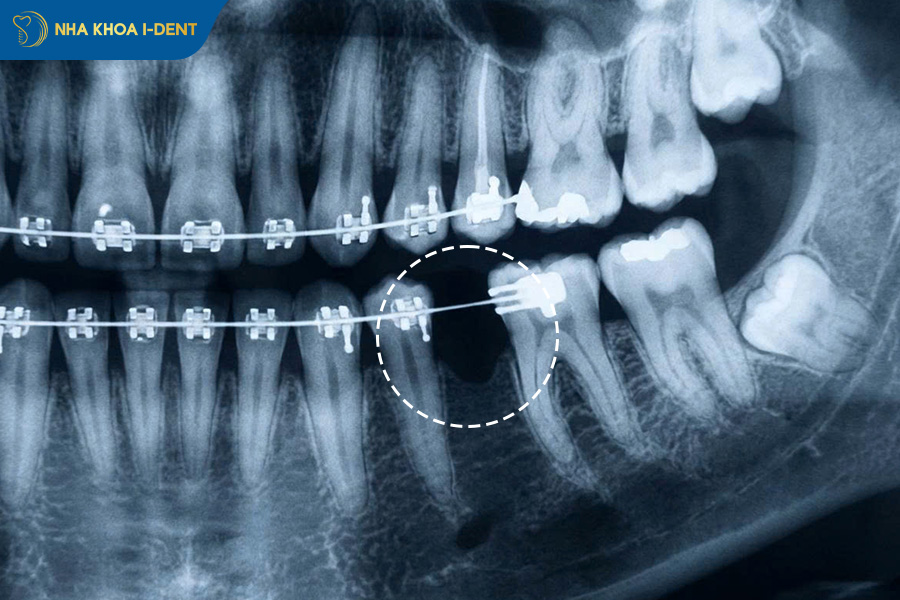

Chết tủy và rụng răng là biến chứng nghiêm trọng nhất nếu niềng răng giá rẻ, kém chất lượng. Nếu bác sĩ không có chuyên môn cao, điều chỉnh lực chỉnh nha quá mạnh hoặc tác động không kiểm soát làm phá hủy hệ thống mạch máu và dây thần kinh bên trong tủy răng, dẫn đến răng mất sức sống, nghiêm trọng hơn là rụng răng hoàn toàn.

Niềng răng 5 triệu giá rẻ làm tăng nguy cơ chết tủy và rụng răng.

1.7. Nguy cơ tiêu xương ổ răng và chân răng

Tiêu xương ổ răng và chân răng là biến chứng nghiêm trọng không kém, xảy ra khi lực chỉnh nha không đúng cách làm phá hủy xương hàm nhanh hơn tốc độ tái tạo, dẫn đến mất xương vĩnh viễn, răng lung lay và cuối cùng là mất răng vĩnh viễn. Nếu tiêu xương răng nghiêm trọng thì việc phục hồi sau này rất khó khăn và tốn kém hơn rất nhiều.

Biến chứng niềng răng 5 triệu giá rẻ làm tăng nguy cơ tiêu xương ổ răng.